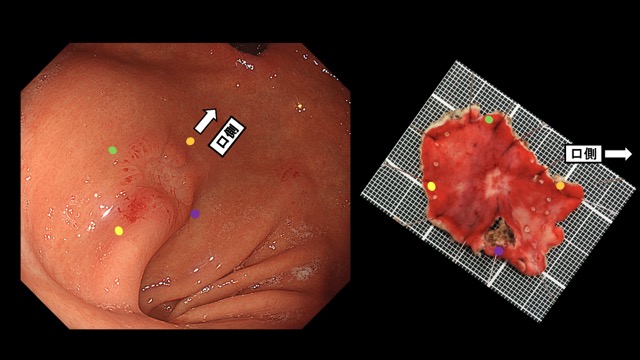

胃001